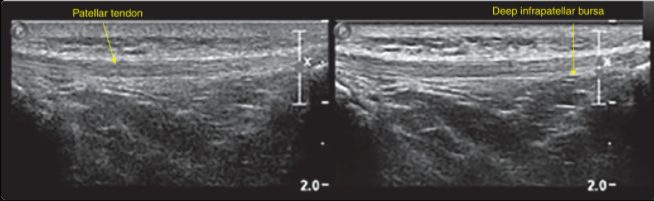

Name the 3 components of spatial resolution in ultrasound?